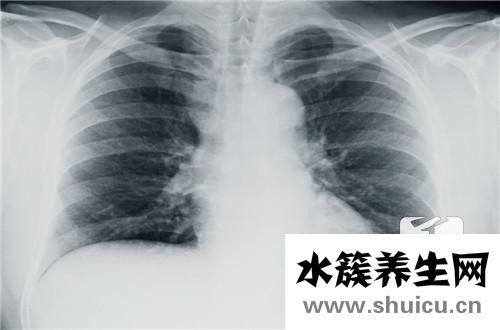

食管癌在醫(yī)藥學(xué)上又叫食道癌,全是消化道上的惡變腫瘤。假如要談起食管癌早期癥狀,很多人或許都能想起消化系統(tǒng)有關(guān)的病癥,此外,胸骨后和劍突下疼痛,是食管癌的早期癥狀在讓你警告。

胸骨后和劍突下疼痛是食管癌較易患的早期癥狀。其特性可呈灼燒樣、扎針樣或伸展樣,主要表現(xiàn)為吞咽食材時有胸骨后或劍突下痛,以吞咽不光滑、炙熱或有含有刺激性的食物為著。疼痛多可被解痙劑臨時減輕。始初呈間斷性,當(dāng)癌瘤侵犯到周邊組織或有透過時,就會有強烈而持續(xù)的疼痛。疼痛位置常不徹底與食道內(nèi)變病位置一致。

極少數(shù)患者可有胸骨后悶脹不適感、前痛和喛氣等病癥。